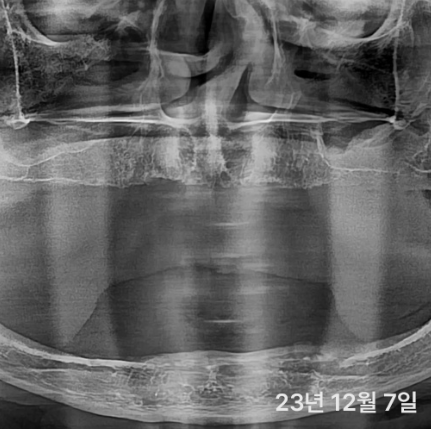

대부분 앞쪽에는 뼈가 있어서

틀니 오래 끼신 분도

이렇게 기존에서 심으면 가능한 경우가 많아요

더군다나 디지털 가이드를 이용해서

뼈가 얇은 경우에도 정확하게 심을 수 있어요